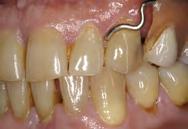

Figura 4. Aspecto de los pilares después de la aplicación de la radiofrecuencia. Arco dentario superior e inferior.

Para realizar el desplazamiento gingival se seleccionó en onda parcialmente rectificada (coagulación), potencia baja (2), y se conectó la punta de trabajo en fulguración. El pedal se activó solo cuando la punta de trabajo estuvo muy cerca del contacto con el tejido.

Se pasó la punta seleccionada, únicamente en contacto con el tejido blando cerca del surco gingival en cada pilar preparado (Figura 3). Cuando la punta se encontró en contacto con el tejido, se mantuvo en movimiento constante para evitar el calor excesivo; el movimiento fue en una sola dirección. En el caso del desplazamiento gingival, el diente se tomó como guía para el electrodo.